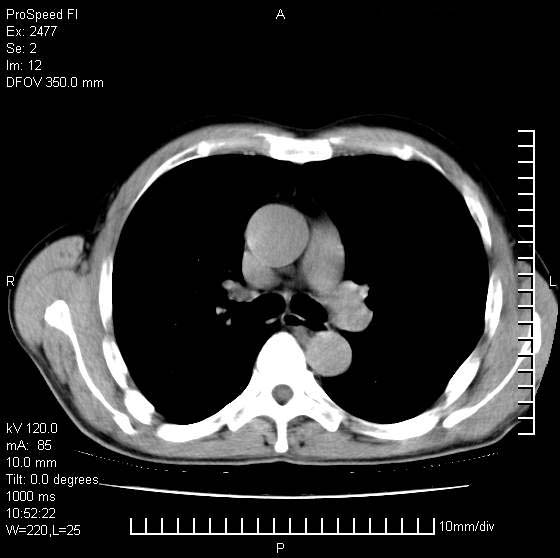

以下是引用天南地北在2007-10-9 14:29:00的发言:[br]1:右上肺结核[br]2:右肺下叶肿块:不支持肺癌,首先考虑炎性病变-肺脓疡可能性大[br]理由:1:临床病史支持,肺脓肿症状不明显应该是不规则服药造成。[br] 2:肿块边缘模糊,周围可见炎性渗出,长毛刺,内见支气管征,不过有点不规则。[br] 我感觉下肺癌这个诊断有点偏左,建议积极抗炎治疗后复查

以下是引用卜一在2007-10-9 15:55:00的发言:[br][br] [br] 1:右上肺结核[br]2:右肺下叶肿块:不支持肺癌,首先考虑炎性病变-肺脓疡可能性大[br]理由:1:临床病史支持,肺脓肿症状不明显应该是不规则服药造成。[br] 2:肿块边缘模糊,周围可见炎性渗出,长毛刺,内见空气支气管征,不过有点不规则。[br] 我感觉下肺癌这个诊断有点偏左,建议积极抗炎治疗后复查![br]支持! [br] [br] [br]

以下是引用wxy7406在2007-10-9 21:02:00的发言:[br]结合临床病史首先考虑感染性病变,但周围型肺癌不能除外,1.患者年龄偏大2.临床有咯血3.(也觉得是最重要的一点)病灶内有偏心性空洞。

以下是引用王仕学在2007-10-9 13:48:00的发言:[br]右下肺周围性肺癌可能性大,最好活检吧

以下是引用hhcckk在2007-10-9 15:18:00的发言:[br]右上肺病灶考虑结核,病灶多种形态并存(纤维化、增殖性病灶并存)[br]右下肺病灶比较难说,个人意见更趋向于“天南地北”的诊断----肺脓肿[br]1、病人有明显的寒战,高热,肿瘤病人很少出现[br]2、病灶周围的肺纹理走向柔和,没有肿瘤病灶常见的集束征[br]3、病灶边缘的毛刺较长,恶性肿瘤多为短毛刺[br]痰中血丝和病人的年龄是两个不利于良性肿块的因素,建议早点活检

以下是引用ydx_74在2007-10-9 15:53:00的发言:[br]右上肺结核,右下中心性肺癌可能大,肺门淋巴结肿大。